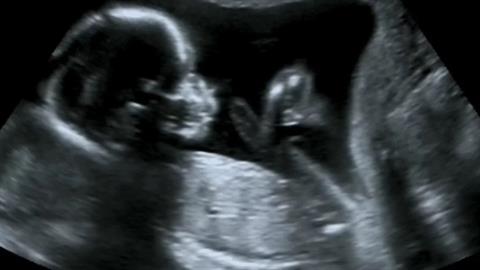

Έμβρυο

Μάθε ποια είναι τα στάδια ανάπτυξης του νευρικού συστήματος του εμβρύου σου και πώς θα μπορέσεις να συμβάλλεις στην καλύτερη δυνατή εξέλιξή του